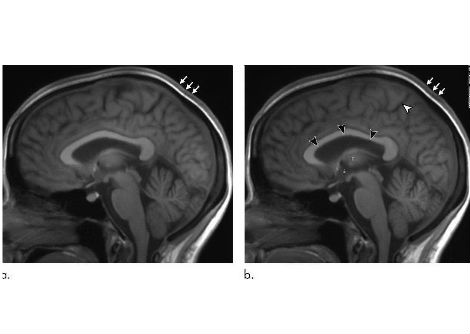

نسيج دماغ بشري مُستأصل، مُجمد بعد 100 مللي ثانية من التحفيز، يُظهر بنيةً داخلية. مقياس الشريط = 100 نانومتر.

في الدراسة الجديدة، استخدم الباحثون عينات من أدمغة فئران سليمة، بالإضافة إلى أنسجة قشرية دماغية حية أُخذت بإذن من ستة أفراد يخضعون لعلاج جراحي للصرع في مستشفى جونز هوبكنز. كانت الإجراءات الجراحية ضرورية طبيًا لإزالة الآفات من حُصين الدماغ.